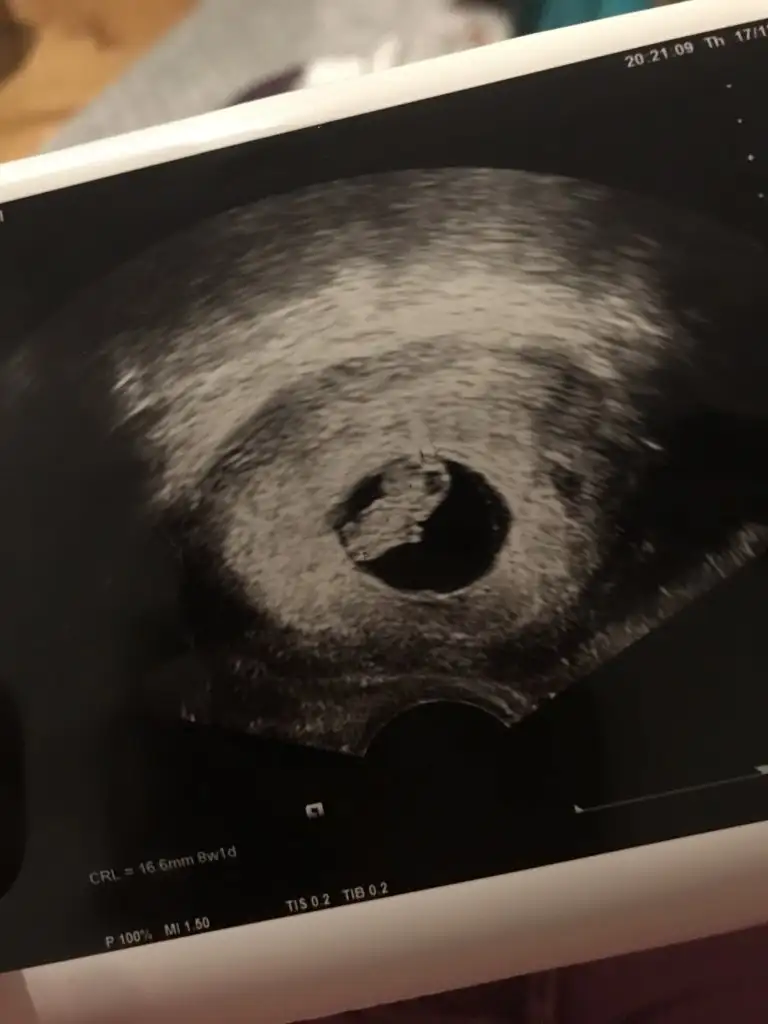

Canlar benimki küçük ama foto net bakabilir misinizIkra meyra 8 haftalık burda Eki Görüntüle 2749923